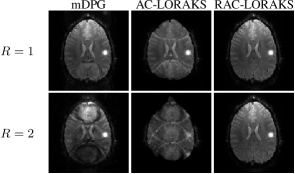

Figure 7 shows reconstruction results from the second set of in vivo diffusion EPI brain acquisitions (with different acceleration factors), with zoom-ins shown in Supporting Information Fig. S9 for improved visibility. Consistent with the results shown for the gradient-echo EPI data in Fig. 1, we observe that all methods perform well for low acceleration factors. As the acceleration factor increases, the performance of each method degrades, with RAC-LORAKS showing a lower qualitative degradation in comparison to the other methods at the very high acceleration factors . Note that at high acceleration factors (e.g., ) the reconstruction quality for RAC-LORAKS is not quite as good as for the gradient-echo EPI dataset shown in Fig. 1. We believe that this should be expected, since as mentioned before, diffusion EPI data can be considered more challenging than the gradient-echo EPI data due to SNR issues, eddy current effects, motion-induced phase effects, and contrast mismatches between the ACS and EPI datasets.

Figure 7: ACS data and reconstruction results for in vivo diffusion EPI brain data for different parallel imaging acceleration factors. For improved visualization, zoomed-in versions of these results (corresponding to the spatial region marked with a yellow rectangle in the first column and first row) are shown in Supporting Information Fig. S9. It should be noted that the subject appears to have slightly moved between scans, so that there is not perfect correspondence between anatomical image features across different acceleration factors.

Figure 8: ACS data and reconstruction results for unaccelerated in vivo cardiac EPI data. The two rows show the same results, but the second row has 5 intensity amplification to better highlight the ghosting characteristics.